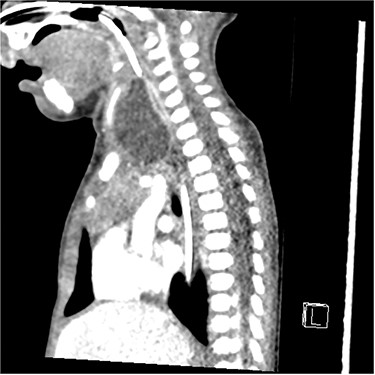

The patient underwent a computed tomography (CT) scan that illustrated a large left-sided supraglottic cyst (3.5 × 2.4 × 2.9 cm) extending from C3 to C7 with paratracheal extension (Figs 1–3). This was confirmed on microlaryngobronchoscopy (MLB) and the cyst was drained. The patient was managed postoperatively in the paediatric intensive care unit where she remained intubated. Extubation was unsuccessful, secondary to worsening stridor and increased work of breathing; a chest X-ray revealed a collapsed right lung. A second MLB was performed and thick bronchial secretions were found, as well as subglottic inflammation, in keeping with a diagnosis of tracheitis.